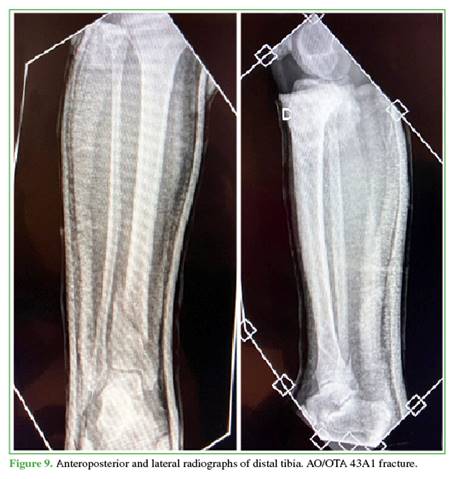

Fractures were classified according to the AO Foundation/Orthopaedic Trauma Association (AO/OTA) system: 11 were type 43A1, 2 were 43A2, 1 was 42A1, and 1 was 42A3. Four of these fractures were open: three Gustilo type IIIA and one type IIIB. These were initially managed with surgical debridement, negative pressure wound therapy, and external fixation. At 48 hours, they were converted to internal fixation with retrograde nailing, and in the IIIB case, a free lateral thigh flap was used for soft tissue coverage.